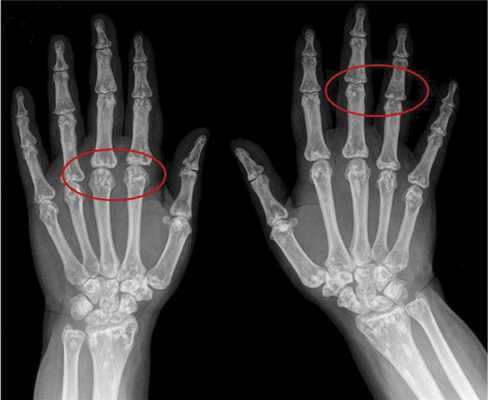

Вторым по частоте встречаемости признаком является поражение костной системы в виде остеопойкилии (синонимы — врожденная рассеянная склерозирующая остеопатия, врожденная пятнистая множественная остеопатия), возникающей в результате очагового отложения кальция [3, 5]. Признаки остеопойкилии обнаруживаются преимущественно в костях конечностей и плечевого пояса. Клинически они не вызывают жалоб, но важны для дифференциальной диагностики. При рентгенологическом исследовании в костях выявляются мелкие округлые или овальные уплотнения спонгиозных структур костной ткани (рис. 2).

Рис. 2. Остеопойкилия.